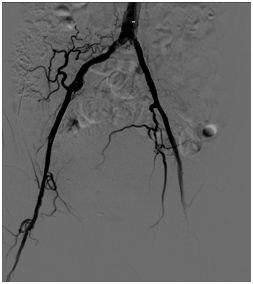

双髂动脉闭塞腔内修复术